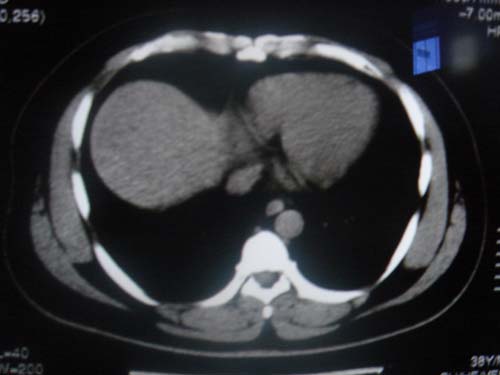

患者 男 40 右上腹不适 有胆囊息肉病史2年

肝脏增大,

片中示肝脏的ct值低于脾脏,肝脏右叶外缘部份凹凸不平,考虑脂肪肝,肝硬化可能。结合其检查如b超或ct增强检查。

肝右叶密度不均,脾大。强烈要求增强扫描除外浸润型肝癌。

肝大   密度降低  脾大  脂肪肝?